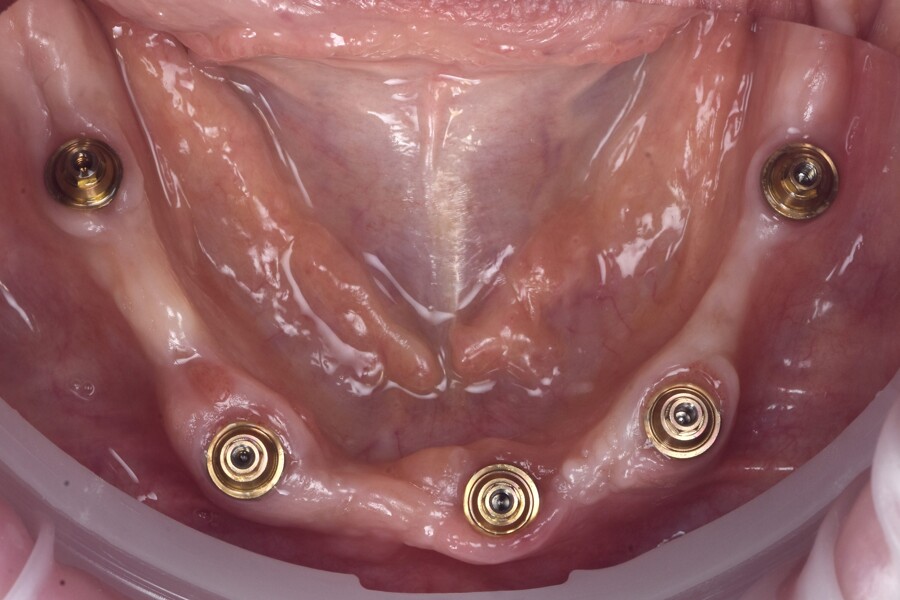

At the surgery appointment, three osteosynthesis screws were placed to facilitate digital alignment of the preoperative and postoperative scans, and the remaining mandibular teeth were extracted, followed by full-thickness flap elevation. Minimal alveolar bone reduction was performed to improve ease of cleaning and to position the transitional line more apically. Five AnyRidge implants (MegaGen) were placed sub-crestally in native bone, avoiding the need for bone grafting (Fig. 4). Straight N-type multi-unit abutments (MegaGen) were connected and torqued to 35 N cm. The further prosthetic workflow was carried out entirely at the abutment level, avoiding implant–abutment disconnections and thereby simplifying the prosthetic procedures (Fig. 5). This approach is favourable for crestal bone stability.

Sufficient primary stability was achieved, enabling immediate loading, consistent with evidence-based recommendations.2–6 SmartFlag scan bodies (Apollo Implant Components) were attached, and the postoperative intra-oral scan was performed with both the scan bodies and the osteosynthesis screws in place (Figs. 6 & 7). The screws were removed after scanning.

Fig. 5: Intra-op photograph after attachment of the osteosynthesis screws and implant placement.